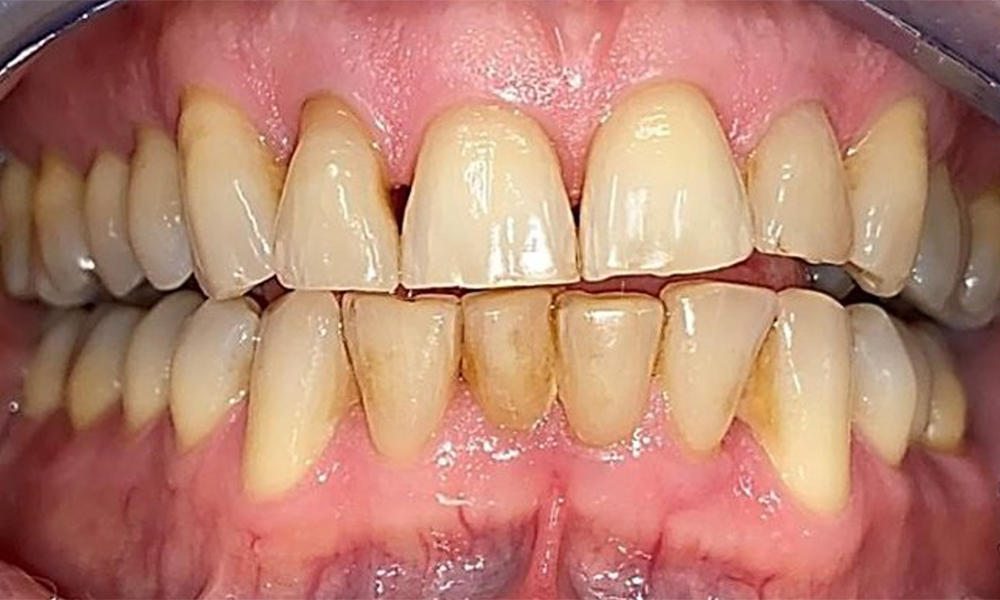

Pacientul prezintă dentiție completă cu 28 de dinți, care include obturații din amalgam și compozit pe molari și premolari. Există un spațiu marginal clinic vizibil la 14. Molarul 27 prezintă un inlay din aur adecvat. Se observă, de asemenea, atriții și abrazii generalizate. (Fig. 2, Fig. 3, Fig. 4, Fig. 5, Fig. 6)

Pacientul prezintă boală parodontală în stadiul II, gradul B (5). Profunzimile clinice de sondare observate, între 1 și 3 mm, se încadrează în limitele fiziologice. Localizat, s-au observat profunzimi de 5 mm, la nivel meziopalatin, atât pe 17, cât și pe 27. Se constată recesiuni generalizate de 1-3 mm, cu pierderi parțiale ale papilelor interdentare (Fig. 2, Fig. 3, Fig. 4)